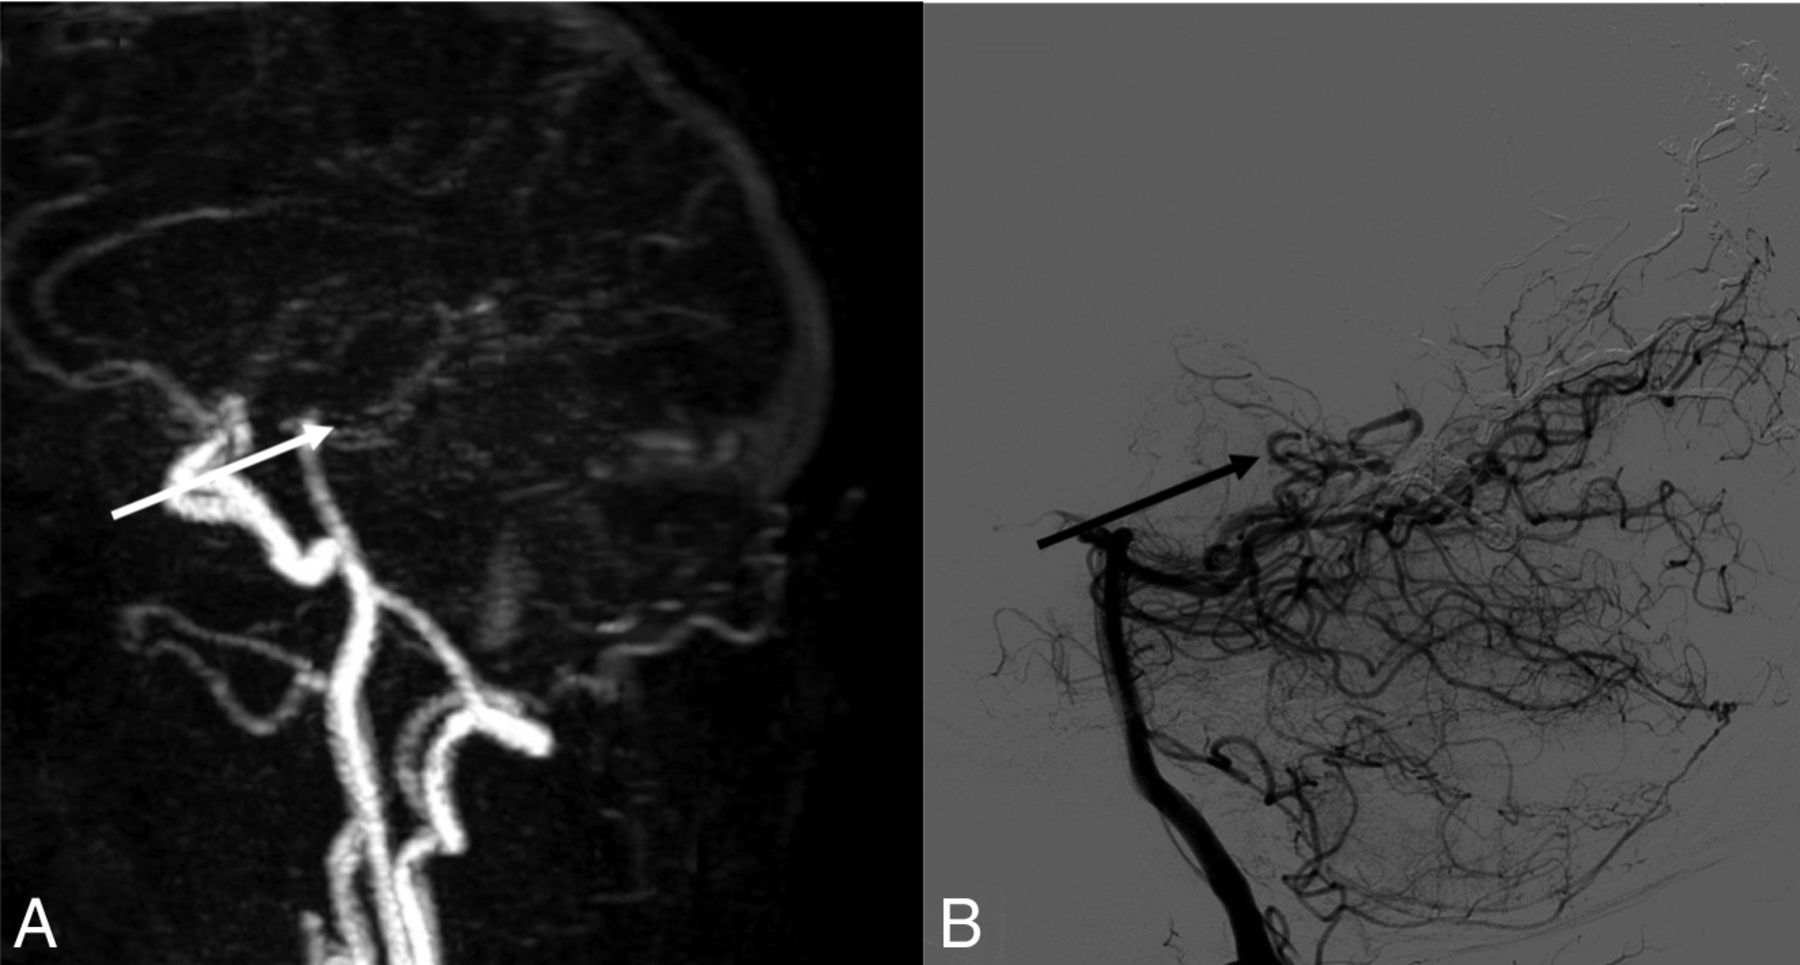

A, Sagittal MIP of 4D-MRA at late arterial phase. B, Cerebral arteriography through the left external carotid artery in a sagittal view. The black arrow in B shows early opacification of an occipital vein, confirming an arteriovenous shunt not found in A.